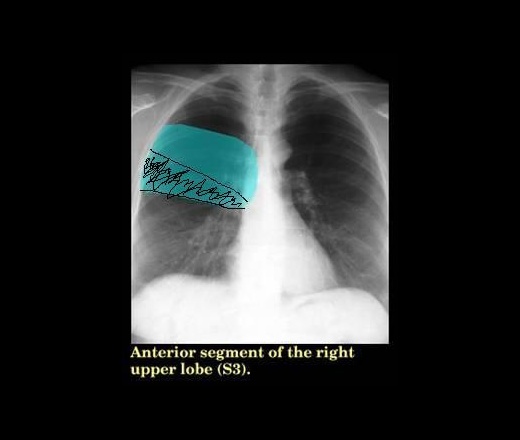

Пациентка около 60 лет, стадает бронхиальной астмой, с жалобами на кашель, слабость, субфебрильную температуру около 1 мес. Около 2 недель назад обратилась к терапевту, при рентгенографии установлен диагноз правосторонней верхнедолевой пневмонии в S3, очень извиняюсь, не могу сегодня представить снимки, на них определялось клиновидной формы однородное затенение в проекции S3 c четкой нижней границей, нарисовала схематически

Во 1-ых: зачем вводить коллег в заблуждение,рисуя схемы на R-граммах другого человека? Разве нельзя было бы изобразить на представленных вначале?

Во 2-ых: что Вы изобразили сплошным зеленым цветом? Опять-заблуждение.

Извините, рисовала на картинках, отображающих сегментарное строение легких, по памяти, она сегодня только снимки принесла. ТМГ нет.